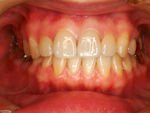

◆オールセラミック修復

~修復後~

オールセラミック修復

~修復後拡大~